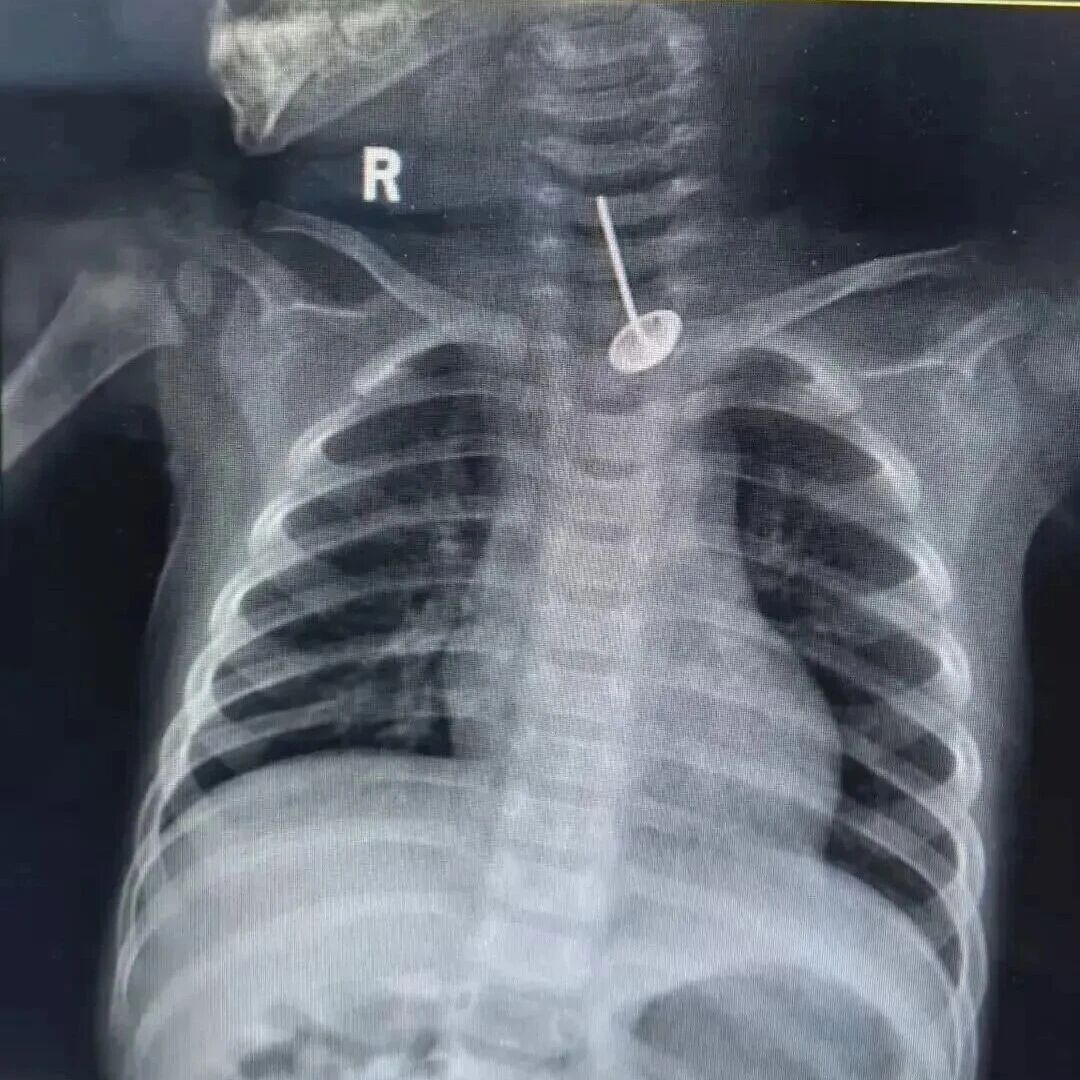

入院后,医生准备为小西实施全麻下口腔内裂伤清创缝合术。然而,就在术前完善胸片检查时,医护人员发现了更加惊险的一幕:小西食管内竟卡着一个图钉样的尖锐金属异物!胸部增强CT检查显示,该异物长达3厘米,已刺破食管壁,尖端紧邻主动脉弓,一旦刺穿大血管,瞬间便会引发大出血,生命危在旦夕。